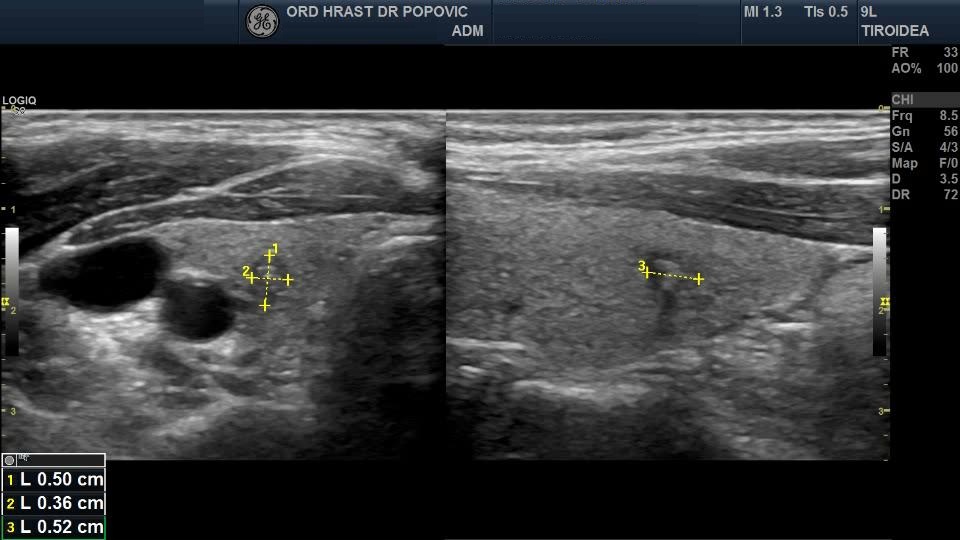

Ultrazvučni pregled štitaste žlezde - Papilarni karcinom štitaste žlezde - ACR TI-RADS 5

Ultrasound examination of the thyroid gland - Papillary carcinoma of the thyroid gland ACR TI-RADS 5